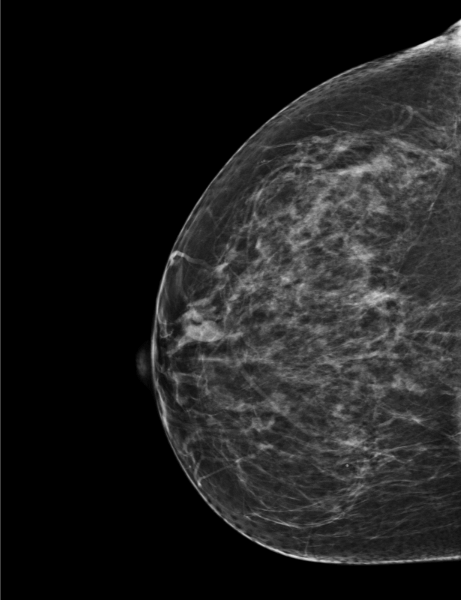

Femme de 60 ans, examinée pour tuméfaction supéro-externe du sein gauche.

MammoScreen™ pointe une masse suspecte (Score de 5) du sein gauche.